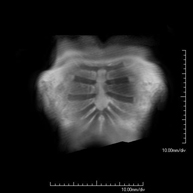

- RM Cerebral (craneal)

Prueba diagnóstica no invasiva que consiste en la obtención de imágenes de alta definición anatómica del cerebro mediante el empleo de un campo electromagnético y ondas de radio (con un emisor y un receptor). No utiliza radiación ionizante. Indicaciones: problemas vasculares, pérdida de memoria, epilepsia, cefalea, malformaciones, sospecha de tumor, meningitis.